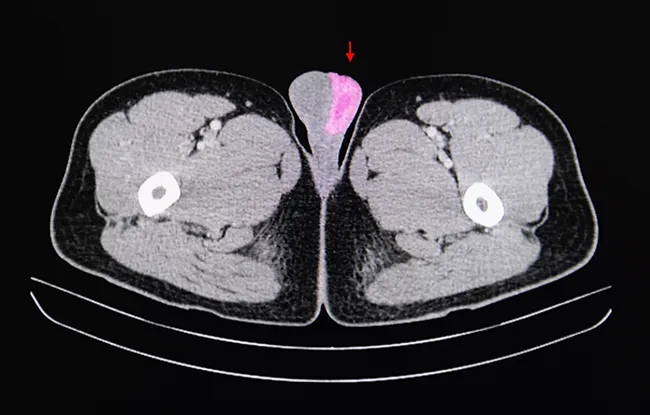

Cancer des testicules

- Cancer des testicules >